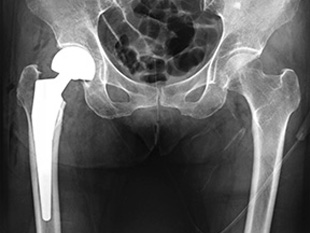

人工骨頭挿入術(大腿骨)

股関節を展開して骨折した大腿骨頭を摘出して人工骨頭(金属・セラミック・ポリエチレンの複合体)に置換えます。固定のために必要な場合は、骨セメント(接着剤)を使用することもあります。

高齢者や骨折部のズレ(転位)が大きい場合は、疼痛のコントロールと早期離床によるADLの改善、介護負担の軽減や合併症の発生・増悪の予防による生存率の向上等につながることから、この術式が適応します。

• 画像:人工骨頭挿入術(大腿骨)